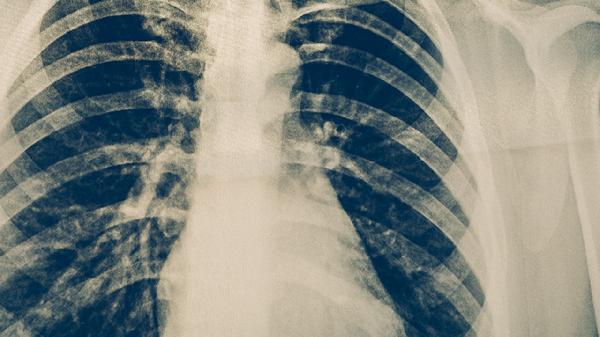

影像學(xué)改善是關(guān)鍵客觀指標。胸部X線或CT檢查顯示原有浸潤性病灶、空洞等病變顯著吸收縮小,纖維條索影形成或鈣化。病灶穩(wěn)定指治療結(jié)束后多次復(fù)查影像學(xué)無進展變化??斩撮]合和炎癥吸收說明病灶內(nèi)細菌數(shù)量大幅減少,但部分患者可能遺留纖維化瘢痕。